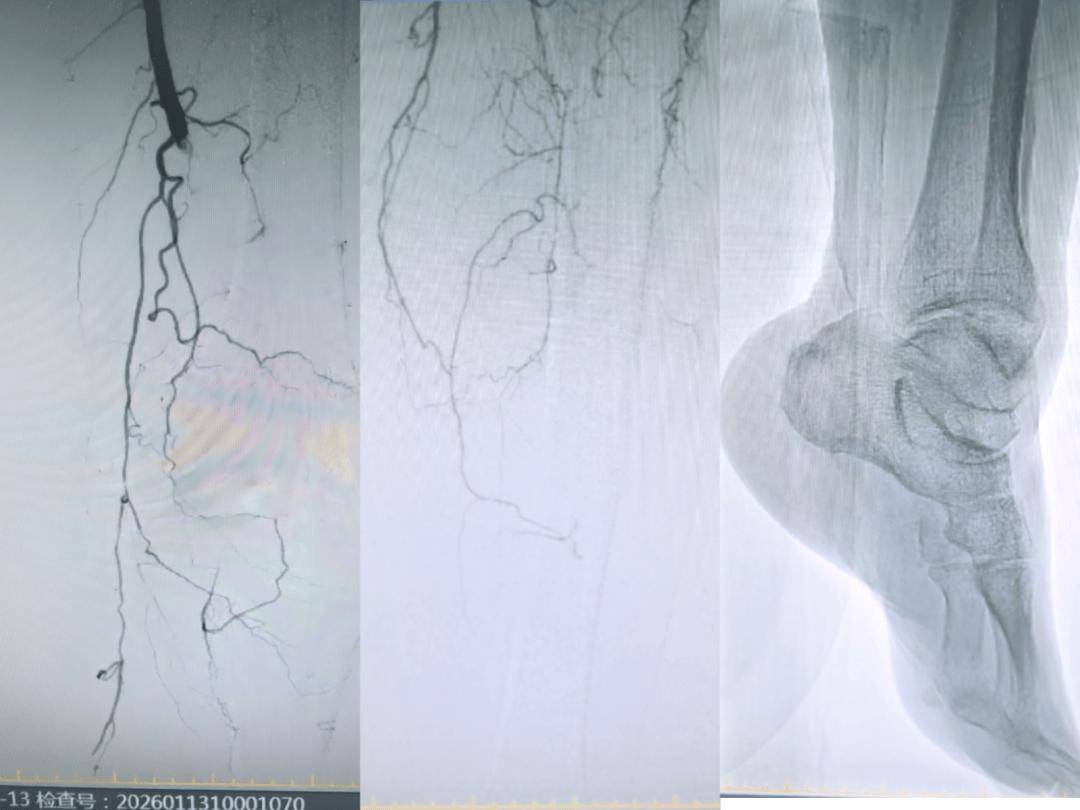

第一阶段是急诊手术,应用减容装置抽出堵塞血管的斑块和血栓,然后再置管溶栓。首先在导管室医护人员配合下,血管外科张君主任在谷涌泉教授的指导下利用微创技术,开通闭塞的股浅动脉、腘动脉、胫前动脉、胫后动脉及足底动脉弓,然后应用动脉减容装置“血管盾构机”进行闭塞血管内减容,最后植入溶栓导管把残留的血栓进行溶栓治疗。

第二阶段是二期手术、彻底通畅。三天后经过留置溶栓导管的持续溶栓治疗,陈旧性血栓被溶解,但血管仍有严重残余狭窄。血管外科团队抓住时机,球囊扩张、无支架技术等微创手段多管齐下,细致处理病变血管,最后造影结果满意。